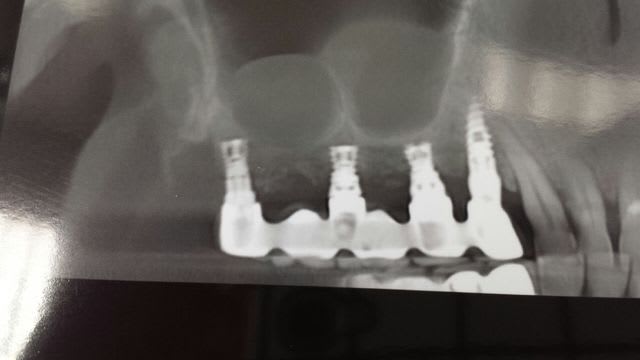

Nom et marque de cet implant EXTRAORDINAIRE?

J'ai pas plus d'infos pour le moment c'est un ami qui a mis ca sur facebook.

Maintenant ca peut dater des annees 80 dces implants et alors la plus personne ne doit rire, mais applaudir

comme d'hab, je donne les infos...;-)

http://www.sargondentalimplants.com/

en tout cas belle pano!!

c'est une sorte de bride complet implanto-dento-porté amovible... mais amovible avec les dents !!! =)

la VRAI question c'est: ça date de quand ?

Si ça date de 1984 c'est un travail remarquable. Si c'est de 2004......

Le fabriquant donne quel protocol pour la dépose ?

Il faut faire un lambeau et meuler latéralement pour le sortir ? Dans les secteur postérieur mandibulaire on fait comment ?

Dans le principe c'est vrais que ça dois assurer une bonne stabilité primaire, mais le prix me semble trop élever par rapport au délabrement osseux nécessaire pour le sortir en cas d’échec.

Il y a des infos sur le taux de fracture a moyen long terme ?

Je m'appelleThierry MSIKA, responsable commercial en Israel de l'implant Quad, fabrique par Dentack.

Quad est disponible en plusieurs dimensions 4.1x5 4.1x6 4.1x7 ou 3.75x7 ( voir photo ci-joint).

A la difference de l'implant presente sur la pano par Matten, l'expansion de l'implant Quad s'arrete lorsqu'elle atteint son maximum. Aussi, l'expansion n'est que de quelques dixiemes de millimetre.